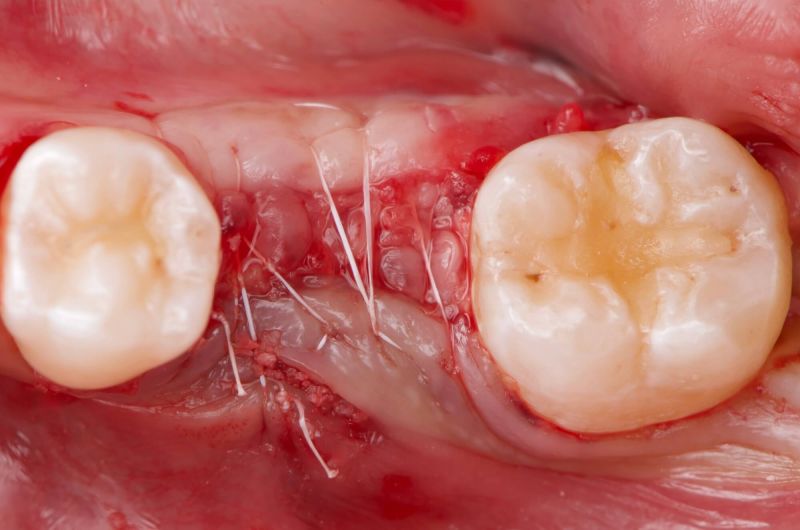

Atraumatic Extraction, Bone Grafting and Implant Placement

Our periodontist removed this damaged tooth and added bone to preserve the area. Four months later, a dental implant was carefully placed followed by a new tooth for optimal chewing and appearance.